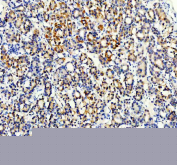

IHC staining of FFPE human breast cancer tissue with STXBP4 antibody, HRP-secondary and DAB substrate. HIER: boil tissue sections in pH8 EDTA for 20 min and allow to cool before testing.